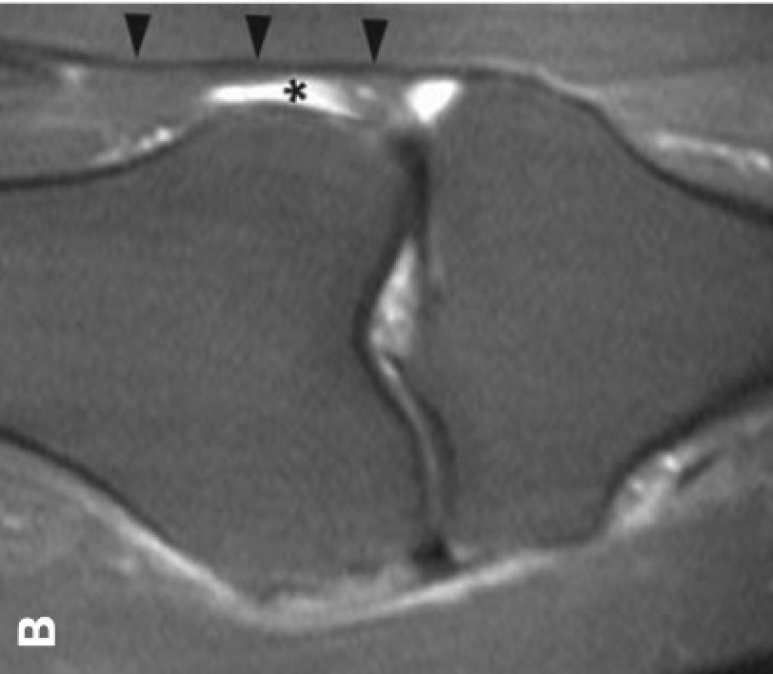

MRI에서는

검정 화살촉으로

표시한 부위가

장경인대구요.

마찬가지로

인대에 염증이 생기면

- 표시한 부위에

삼출액이 고이게 됩니다.

여기서

더 만성화되면

인대가 퉁퉁 부어

두꺼워지고

뼈도 울퉁불퉁

변형이 오게 됩니다.